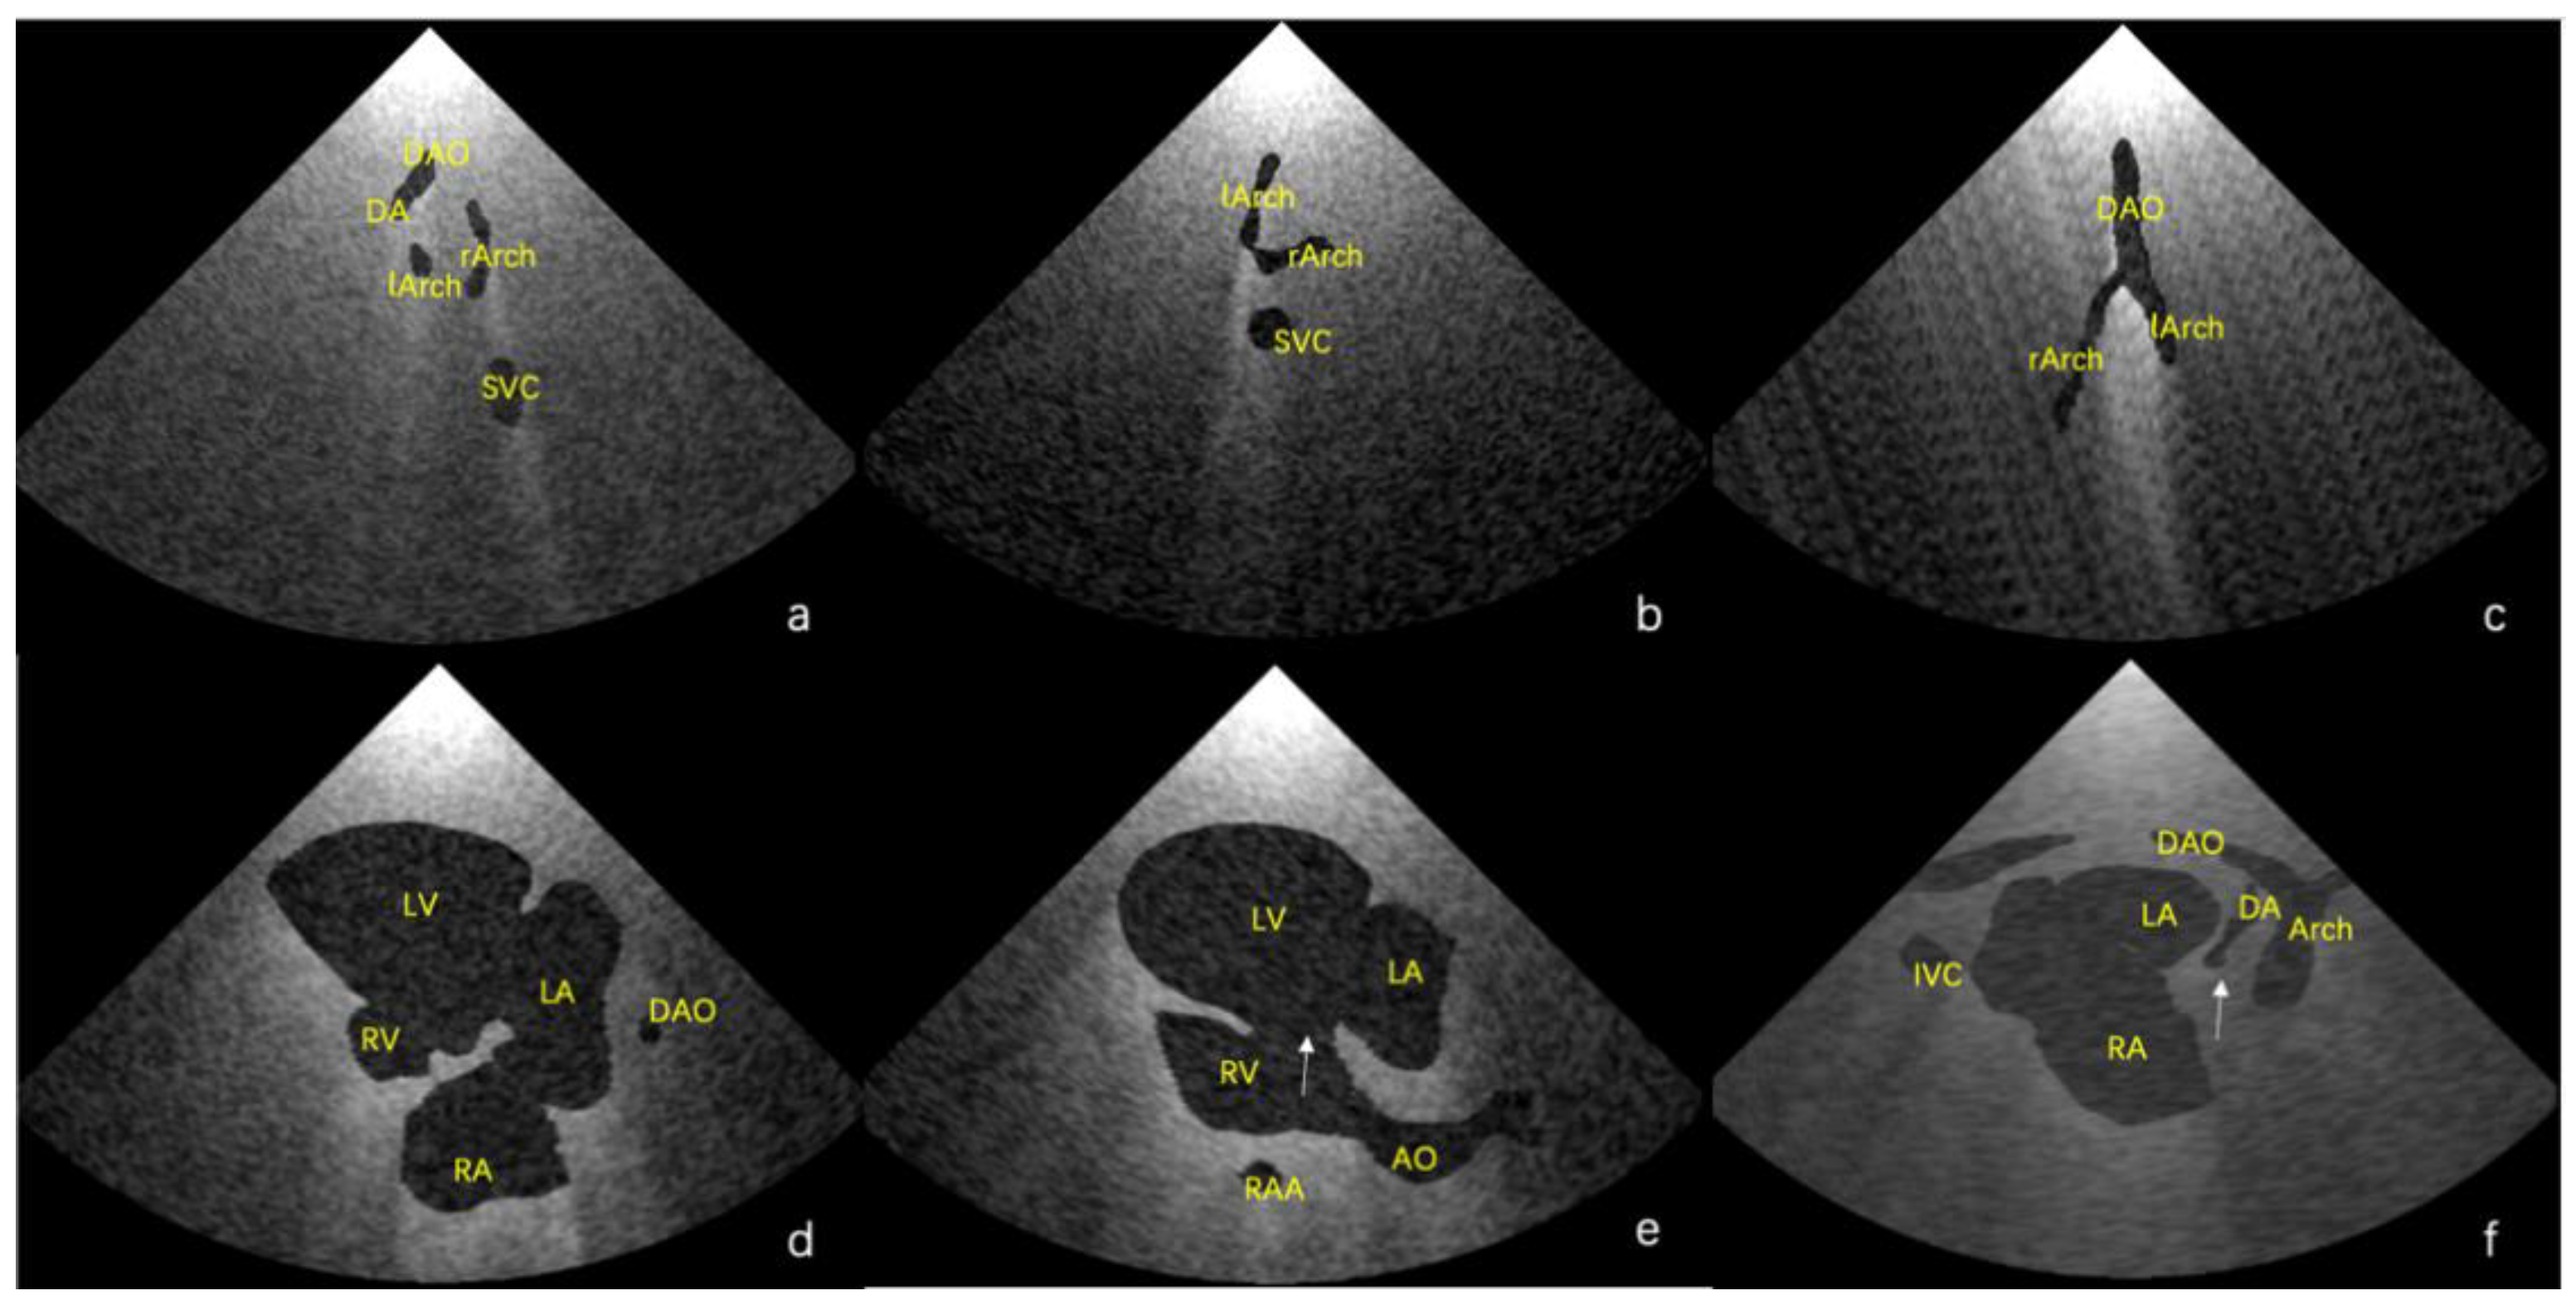

Using the final scenes, eight main standard views (four-chamber view, left ventricular outflow tract view, right ventricular outflow tract view, three-vessel view, three vessels and trachea, aortic arch view, ductal view, and bicaval view) [23,24] and additional views in which the lesion was adequately demonstrated could be obtained. Examples of standard views for the normal heart are shown in Figure 3, and example views with diagnostic values for the two abnormal hearts are shown in Figure 4. As shown in Figure 4a, there is an abnormal vessel between the DA and the aortic arch in the three vessels and the trachea view. In Figure 4b, the probe moves toward the cephalic side of the fetus from the three-vessel trachea view to show a cross-section of the double aortic arches. In Figure 4c, the double aortic arch connects the descending AO at the coronal level. In Figure 4d, the RV is significantly smaller than the LV in the four-chamber view. In Figure 4e, there is a channel between the left and right ventricles (indicated by the arrow), and the AO arises from the RV. In Figure 4f, the initial part of the PA is not connected to the ventricle (indicated by the arrow).

Figure 4. (ac) Lesion-sensitive virtual views of the double-aortic arch for Case 2; and (df) hypoplasia of the right heart, ventricle septal defect, malposition of the great arteries, and pulmonary atresia for Case 3.